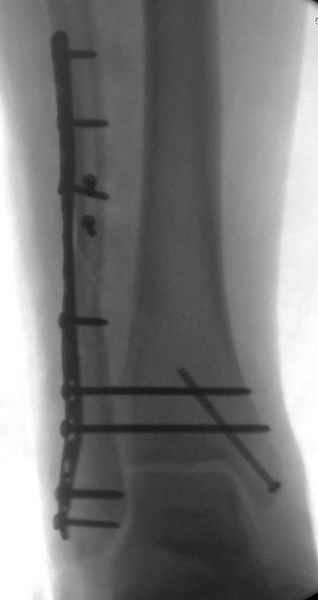

С мнением «провести позиционный межберцовый винт чуть ниже пластинки в положениий тыльного сгибания стопы» согласен, но я бы нагрузку начал через три недели и удаление шурупа можно провести через 6-8 недель.

Для облегчения удаления сломанных шурупов (случается часто) рекомендую фиксацию двумя 3.5мм кортикальными шурупами на 3 мм длиннее, тот же сломанный шуруп легко удаляется с медиальной стороны.

Здесь похожий случай трехнедельной давности, перелом почти сросся и была укорочена малоберцовая, на операции длину малоберцовой смогли восстановить только после того, когда проксимальнее пластины ввели шуруп и использовали его как толкатель, с помощбю дистракционого инструмента (lamina spreader).

Меньше всего волнует положение медиальной лодыжки - в любое время можно провести остео или реостеосинтез, при несращении можно просто резецировать без ущерба для движений в голеностопе. Здесь обошлись фиксацией одним 4 мм канюлированным шурупом.

Перелом позиционного винта (одного 3.5 мм введенного через 3 кортикала) наблюдаем в 15% при ранней нагрузке. Винт, введеный через 4 кортикала полностью блокирует ротационные движения м\б кости, и поэтому его перелом более вероятен.

Неудаленная часть винта проблем (жалоб) не вызывает. Межберцовый винт никогда не проводим через синдесмоз. Только выше на 2-3 см, т.е на 4-5 см выше щели г\ст сустава.